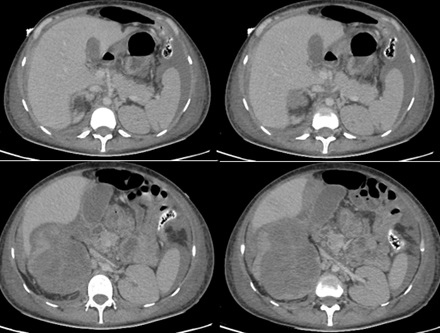

Paciente de 27 años, sexo femenino con antecedentes patológicos de artritis, síndrome de Raynoud, cistitis xantogranulomatosa, glucosuria familiar, anemia ferropénica asociado a cistitis hemorrágica, infecciones urinarias a repetición en los últimos 2 años (4 episodios por año) y hospitalización reciente por candidiuria, tratada previamente. Cursó con cuadro clínico de fiebre no cuantificada, disuria, polaquiuria, reporte de urocultivo ambulatorio con presencia de Klebsiella pneumoniae multisensible, es tratada con control de urocultivo negativo. Laboratorios de seguimiento con hemograma: leucocitos 12.30 ul, hemoglobina 10.60 g/dl, hematocrito 34.50%, plaquetas 297000 mcL, neutrófilos 9.95 ul, linfocitos 1.37 ul, monocitos 0.6ul. Uroanálisis: color rojo, aspecto turbio, PH 6.5, nitritos negativos, glucosa >1000 mg/dl, leucocitos 25-30 xc, hematíes 30-55 xc, células epiteliales 0-2 xc, bacterias escasas. Función renal: BUN 9.50 mg/dl, creatinina 0.81mg/dl. Otros resultados: potasio 4.50 mmol/L, albumina 3.33 g/dl, hierro total 13.00 ug/dl, ferritina 1826.67 ng/ml, proteinuria en 24 horas 618.75 mg/24 horas, proteinuria en orina ocasional 137.5 mg/L, volumen de orina de 24 horas: 4500 ml/24 horas. Durante su seguimiento por nefrología se encontró cuadro clínico de 15 días de evolución caracterizado por persistencia de síntomas urinarios irritativos acompañado de leve distensión abdominal y dolor en hemiabdomen derecho por lo cual ingreso al servicio de urgencias, iniciando manejo farmacológico, vigilancia hemodinámica y control radiológico con ecografía renal con presencia de engrosamiento urotelial, alteración en la ecogenicidad del parénquima del riñón derecho por pielonefritis y/o cambios de nefropatía, además de engrosamiento de las paredes vesicales en relación con cambios inflamatorios, presencia de gas intraluminal, restos hemáticos o detritus en la luz vesical e imágenes que pueden corresponder a restos hemáticos impactados o pólipos. Durante su estancia hospitalaria se observó reactantes de fase aguda en aumento, conservación de la función renal, hemograma con leucocitosis y neutrófilia, anemia moderada hipocromica microcitica, por lo cual se escalonó esquema de antibioticoterapia. Además, se realizaron cultivos de orina de forma seriada encontrando bacilos de Mycobacterium tuberculosis en la cuarta muestra analizada. En su día 5 de hospitalización presento choque hemodinámico, anemización severa aguda, insuficiencia respiratoria severa con requerimiento de hospitalización en unidad de cuidados intensivos (UCI), soporte ventilatorio, vasopresor y transfusión de hemoderivados. Por el deterioro clínico se realizó tomografía computarizada de abdomen y pelvis con impresión diagnostica de laceración del polo superior del riñón derecho con hematoma en el espacio pararrenal anterior, sangrado activo, contusión hepática en el segmento VI, también presencia de cambios de pielonefritis xantogranulomatosa derecha, dilatación ureteral a nivel de la pelvis renal, uréter derecho y engrosamiento vesical (Figura 1 y Figura 2).

Riñón derecho con pérdida de la estructura corticomedular, presencia de líquido libre subhepático y periesplénico compatibles con hemoperitoneo.

Figura 2 Tomografía computarizada de abdomen y pelvis